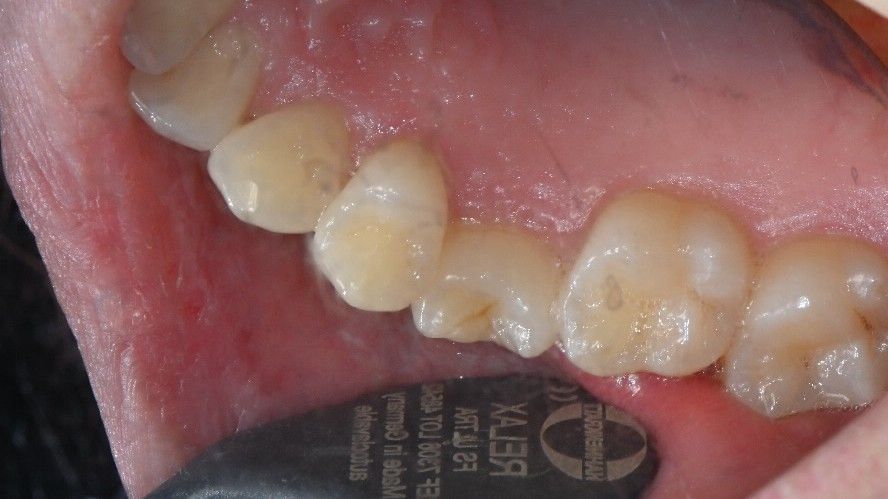

• 2번 째 사진

사진상으로는 특별히 문제가 보이지 않습니다. 치아의 문제가 아닌 신경에 문제가 있을수도 있습니다.

3. 첫번째 큰 어금니, 두번째 작은 어금니 사이에 음식물이 잘 끼어 충치가 잘 유발될 수 있는 구조이므로 치실질 잘해주셔야 합니다.